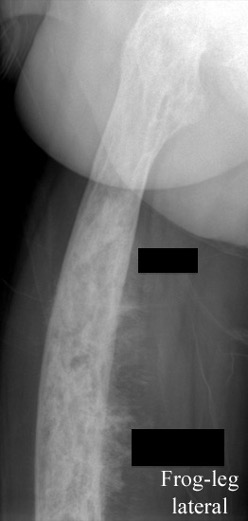

Femur

Tibia

Tibia deformity - sabre tibia